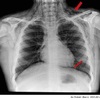

Dx

Neumotorax en pulmón derecho